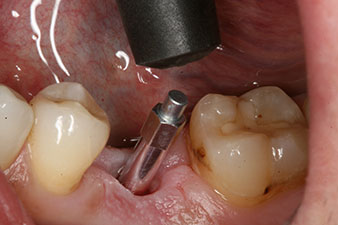

Abb. 4: Eingeschraubter SmartPeg Messpfosten für die Bestimmung des Implantatstabilitäts-Quotienten mit dem integrierten W&H Osstell ISQ Modul.

Das Drehmoment beim maschinellen Einbringen war 43 Ncm. Zusätzlich wurde, nach Einschrauben eines speziellen, auf das Implantatsystem abgestimmten Mess-Pfostens (SmartPeg), der ISQ-Wert mit der Sonde des W&H Osstell ISQ Modul bestimmt.